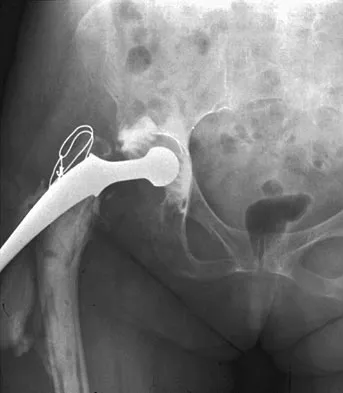

Figure 24 shows the radiograph of an otherwise healthy 56-year-old patient who reports hip pain after undergoing a primary cementless hip replacement 4 months ago. The next most appropriate step should consist of

Periosteal new bone formation is a warning sign of prosthetic infection. Indomethacin may prevent heterotopic ossification if given early enough; however, it is irrelevant in this patient. A C-reactive protein and a sed rate are useful screening studies that add to the predictive value of the radiographs and may be performed routinely if sepsis is suspected. A bone scan obtained 4 months after surgery would show increased uptake in all cases. If results of a sed rate and C-reactive protein are normal, then a biopsy should be considered to rule out a neoplasm.